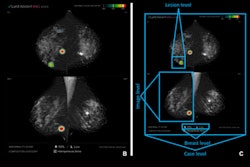

Dr. Jacopo Nori is a widely respected breast imaging specialist from Florence, Italy. In a viewpoint column, he has expressed concern that the lack of education and awareness remains a significant barrier to the adoption of contrast-enhanced mammography.